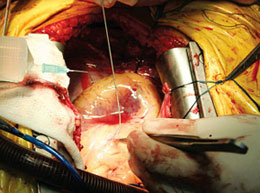

В регіональному центрі кардіохірургії проводяться серцева ендовоскулярні втручання (коропаровентрикулографія, стентування при гострому каронарному синдромі), всілякі операції при порушеннях серцевого ритму.